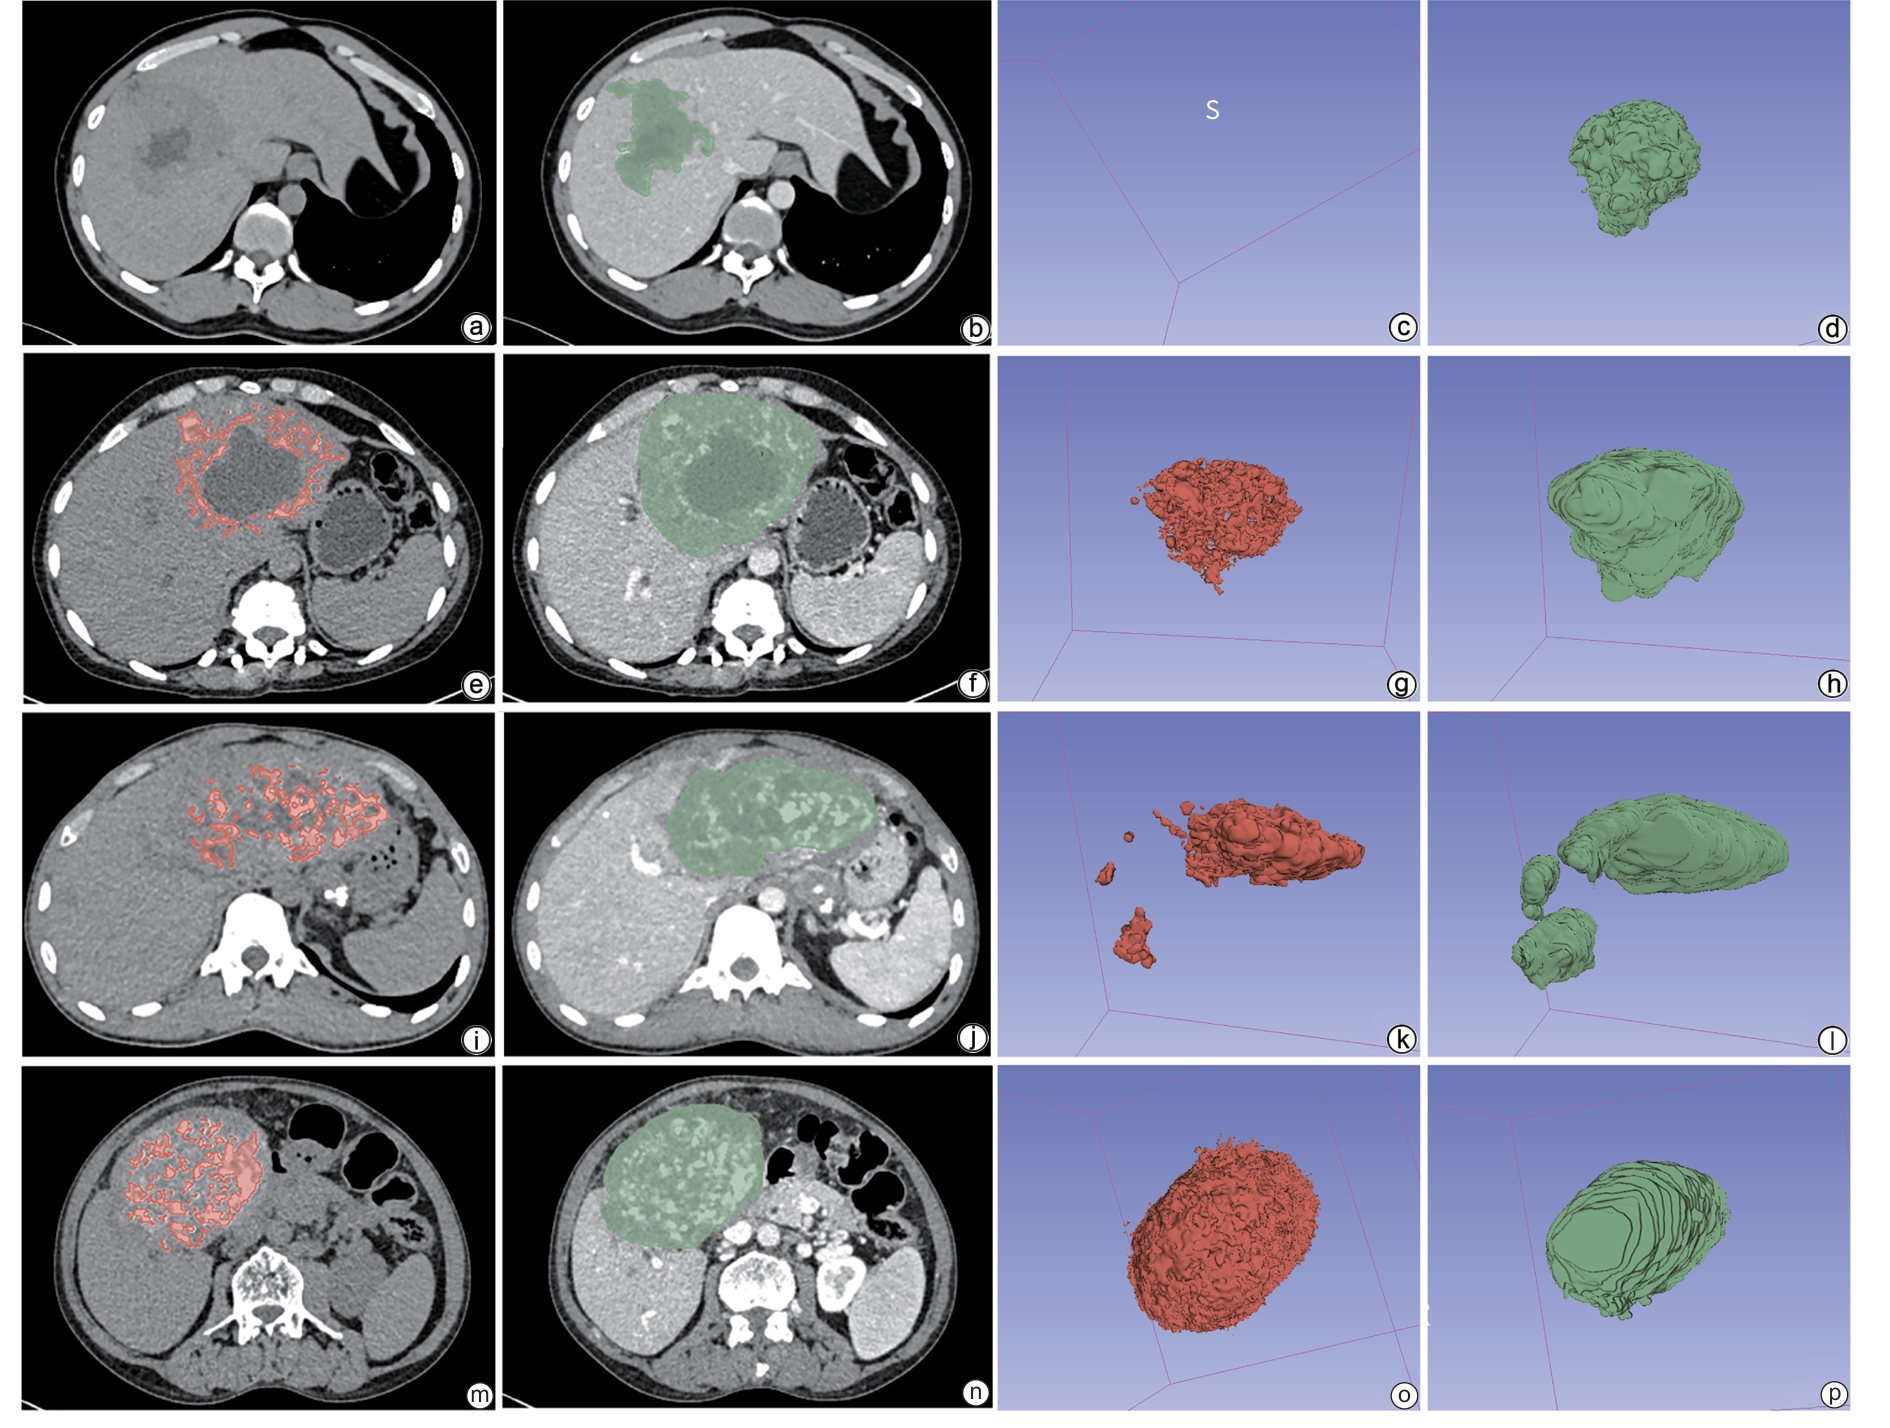

Influencing factors for calcium salt deposition in patients with alveolar echinococcosis

Zitong XIONG, Zhiyi LIN, Yanxin HUANG, Fuzhong FANG, Zhengzhan WU, Zirui XIN, Chunxia HU, Jiayu ZHOU, Yuan YAO, Hongwei ZHANG

2026, 42(2): 372-379. DOI: 10.12449/JCH260217

Abstract:

Objective  To investigate the imaging features of calcium salt deposition and serological markers in patients with alveolar echinococcosis through a retrospective analysis, as well as independent risk factors for the degree of calcium salt deposition in lesions, and to provide a basis for assessing disease process.  Methods  A retrospective analysis was performed for the imaging and clinical data of 107 patients with alveolar echinococcosis who were admitted to The First Affiliated Hospital of Shihezi University from December 2023 to June 2025, and according to the volume of calcium salt deposition, they were divided into non-deposition group with 16 patients, mild deposition group with 52 patients, moderate deposition group with 16 patients, and severe deposition group with 23 patients. A one-way analysis of variance or the Kruskal-Wallis H test was used for comparison of continuous data between groups, and the χ2 test or Fisher’s exact test was used for comparison of categorical data between groups. The four groups were further combined into the low deposition group (no/mild deposition) and the high deposition group (moderate/severe deposition). A binary logistic regression analysis was used to investigate the independent influencing factors for calcium salt deposition, and a predictive model was established. The receiver operating characteristic (ROC) curve was used to assess the predictive performance of the model, and the Bootstrap method was used for internal validation.  Results  There were significant differences between the four groups in sex distribution, involvement of other sites, white blood cell count, lymphocyte percentage, fibrinogen, uric acid, sodium ion, chloride ion, and calcium ion (all P<0.05). The univariate analysis showed that there were significant differences between the four groups in sex, involvement of other sites, white blood cell count, lymphocyte percentage, fibrinogen, alanine aminotransferase, albumin, creatinine, uric acid, sodium ion, chloride ion, and calcium ion (all P<0.1). The multi-collinearity diagnosis showed that the VIF values for all continuous variables ranged from 1.104 to 1.760, suggesting that collinearity did not affect modeling. An ordinal logistic regression model was established based on sex, involvement of other sites, calcium ion, lymphocyte percentage, and uric acid. The multivariate analysis showed that lymphocyte percentage (odds ratio [OR]=1.106, 95% confidence interval [CI]: 1.041 — 1.174, P=0.001) and blood calcium level (OR=0.005, 95%CI: 0.000 —0.230, P=0.007) were independent influencing factors for the degree of calcium salt deposition. The regression equation was established as Logit(P)=8.231 + 0.100 × lymphocyte percentage -5.344 × calcium ion. The ROC curve analysis showed that the model had an area under the ROC curve of 0.716, with a Youden index of 0.353, a sensitivity of 1.000, and a specificity of 0.353. The Hosmer-Lemeshow test showed that the model had poor calibration (χ2=20.688, P=0.008). The Bootstrap method with 1000 repeated samples showed that the estimated values of lymphocyte percentage (OR=1.106, 95%CI: 1.049 — 1.186, P=0.002) and calcium ion (OR=0.005, 95%CI: 0.000 — 0.214, P=0.010) were consistent with the original model, and the confidence intervals did not include 1, which further supported the reliability of the model.  Conclusion  Both lymphocyte percentage and blood calcium level are independent influencing factors for calcium salt deposition in alveolar echinococcosis, and the degree of calcium salt deposition in alveolar echinococcosis lesions increases with the reduction in blood calcium level and the increase in lymphocyte percentage.